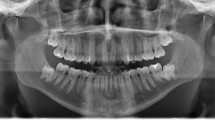

The patient was a 24-year-old woman with a chief complaint of a gummy smile. Although orthognathic surgery was previously recommended, the patient refused to undergo surgery. The pre-treatment smiling facial photograph revealed excessive gingival display (Fig. 1A). Intra-oral photographs revealed a Class I molar relationship, deep overbite, and congenitally missing mandibular right lateral incisor (Fig. 1B). A panoramic radiograph showed existence of all third molars except the maxillary right third molar (Fig. 1C). Accordingly, the patient was diagnosed with a severe deep bite with a gummy smile and missing mandibular right lateral incisor.

(A) Intrusion of the maxillary anterior teeth using an elastic chain from temporary anchorage devices. (B) Intra-oral photograph 12 months after anterior teeth intrusion. The crown of the maxillary right central incisor showed discoloration. (C) Dental x-ray immediately after discoloration of the crown